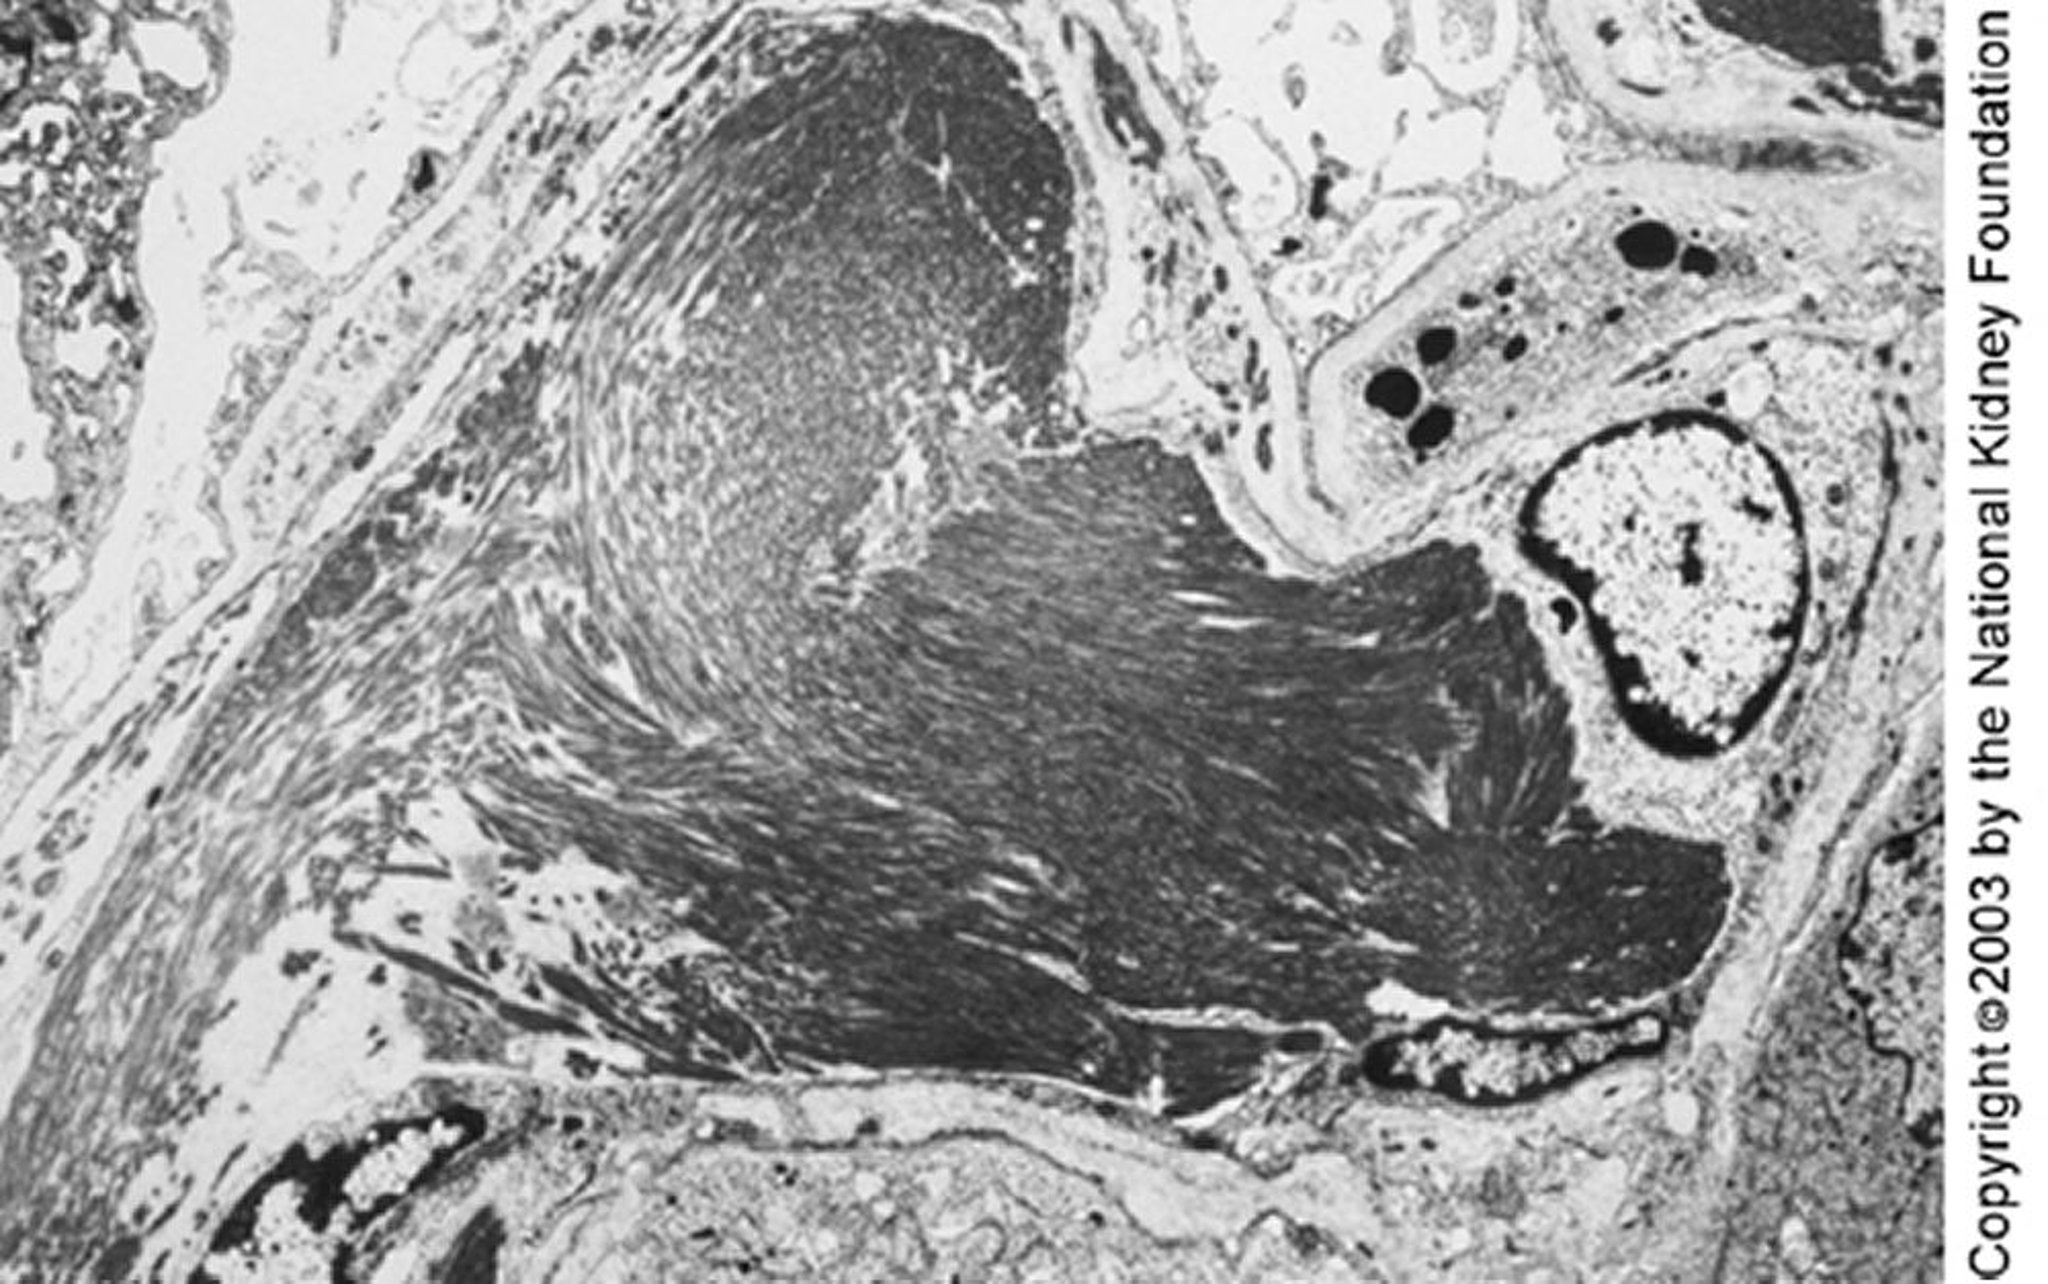

Large microtubules (close to 50 nm in diameter) organized in parallel arrays can be seen on transmission electron microscopy. The parallel deposits and microtubular structure may distinguish immunotactoid from fibrillary glomerulopathy (×4000).

Image provided by Agnes Fogo, MD, and the American Journal of Kidney Diseases' Atlas of Renal Pathology (see www.ajkd.org).